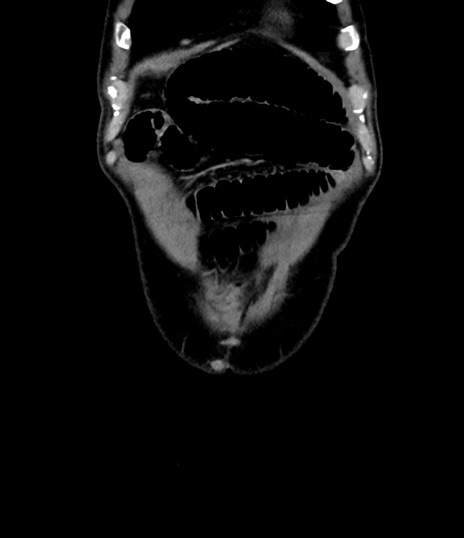

横断像